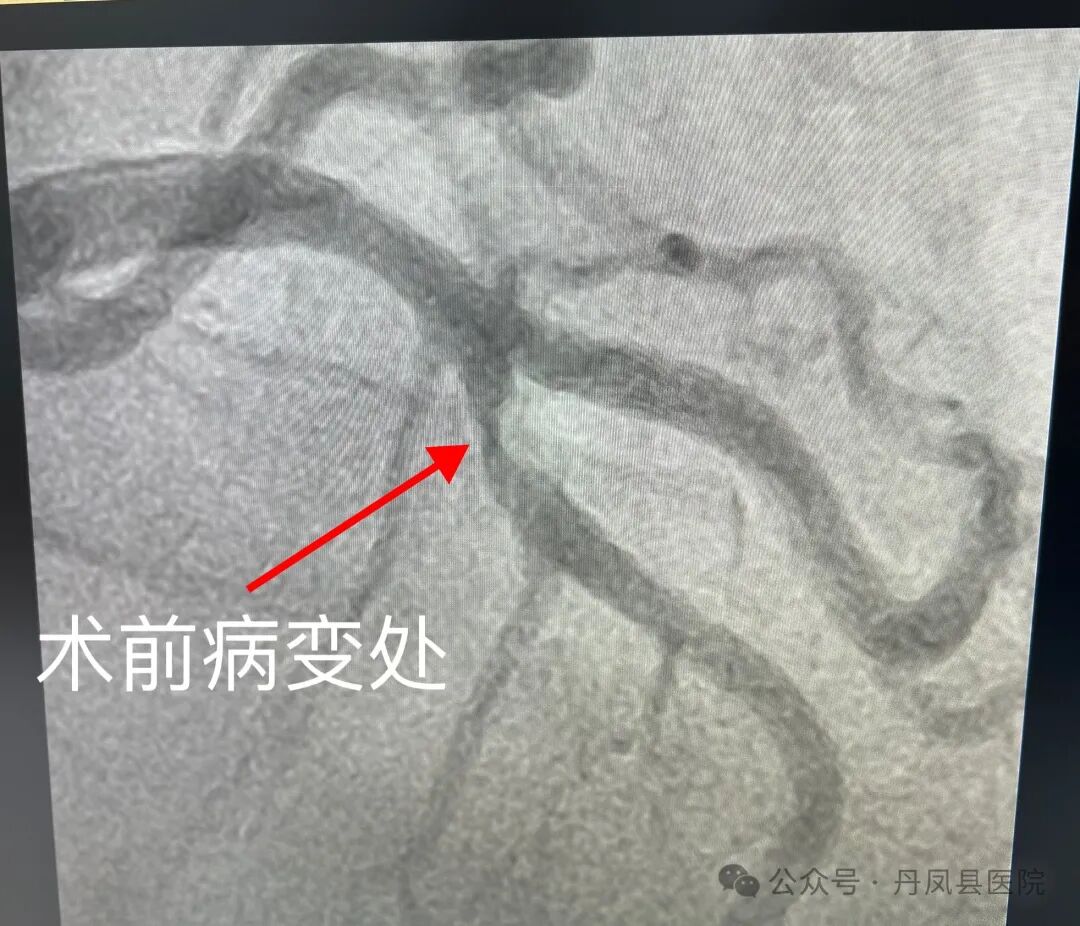

在充分告知患者及家属相关情况后,家属同意行冠脉造影检查。完善术前检查及准备后,于9月10日,心血管内科团队为患者进行了冠状动脉造影术,造影结果显示,LAD第7段粥样硬化斑块浸润,最重处狭窄90%。因前降支病变处于对角支分叉处,为进一步评估病变情况,以及便于术式及支架选择,科室建议使用IVUS检查。IVUS检查显示最重处管腔狭窄84%,遂顺利植入支架一枚。支架植入并扩张后,再次使用IVUS检查,提示支架贴壁良好,无夹层及血肿,手术顺利完成,患者安返病房。![]()